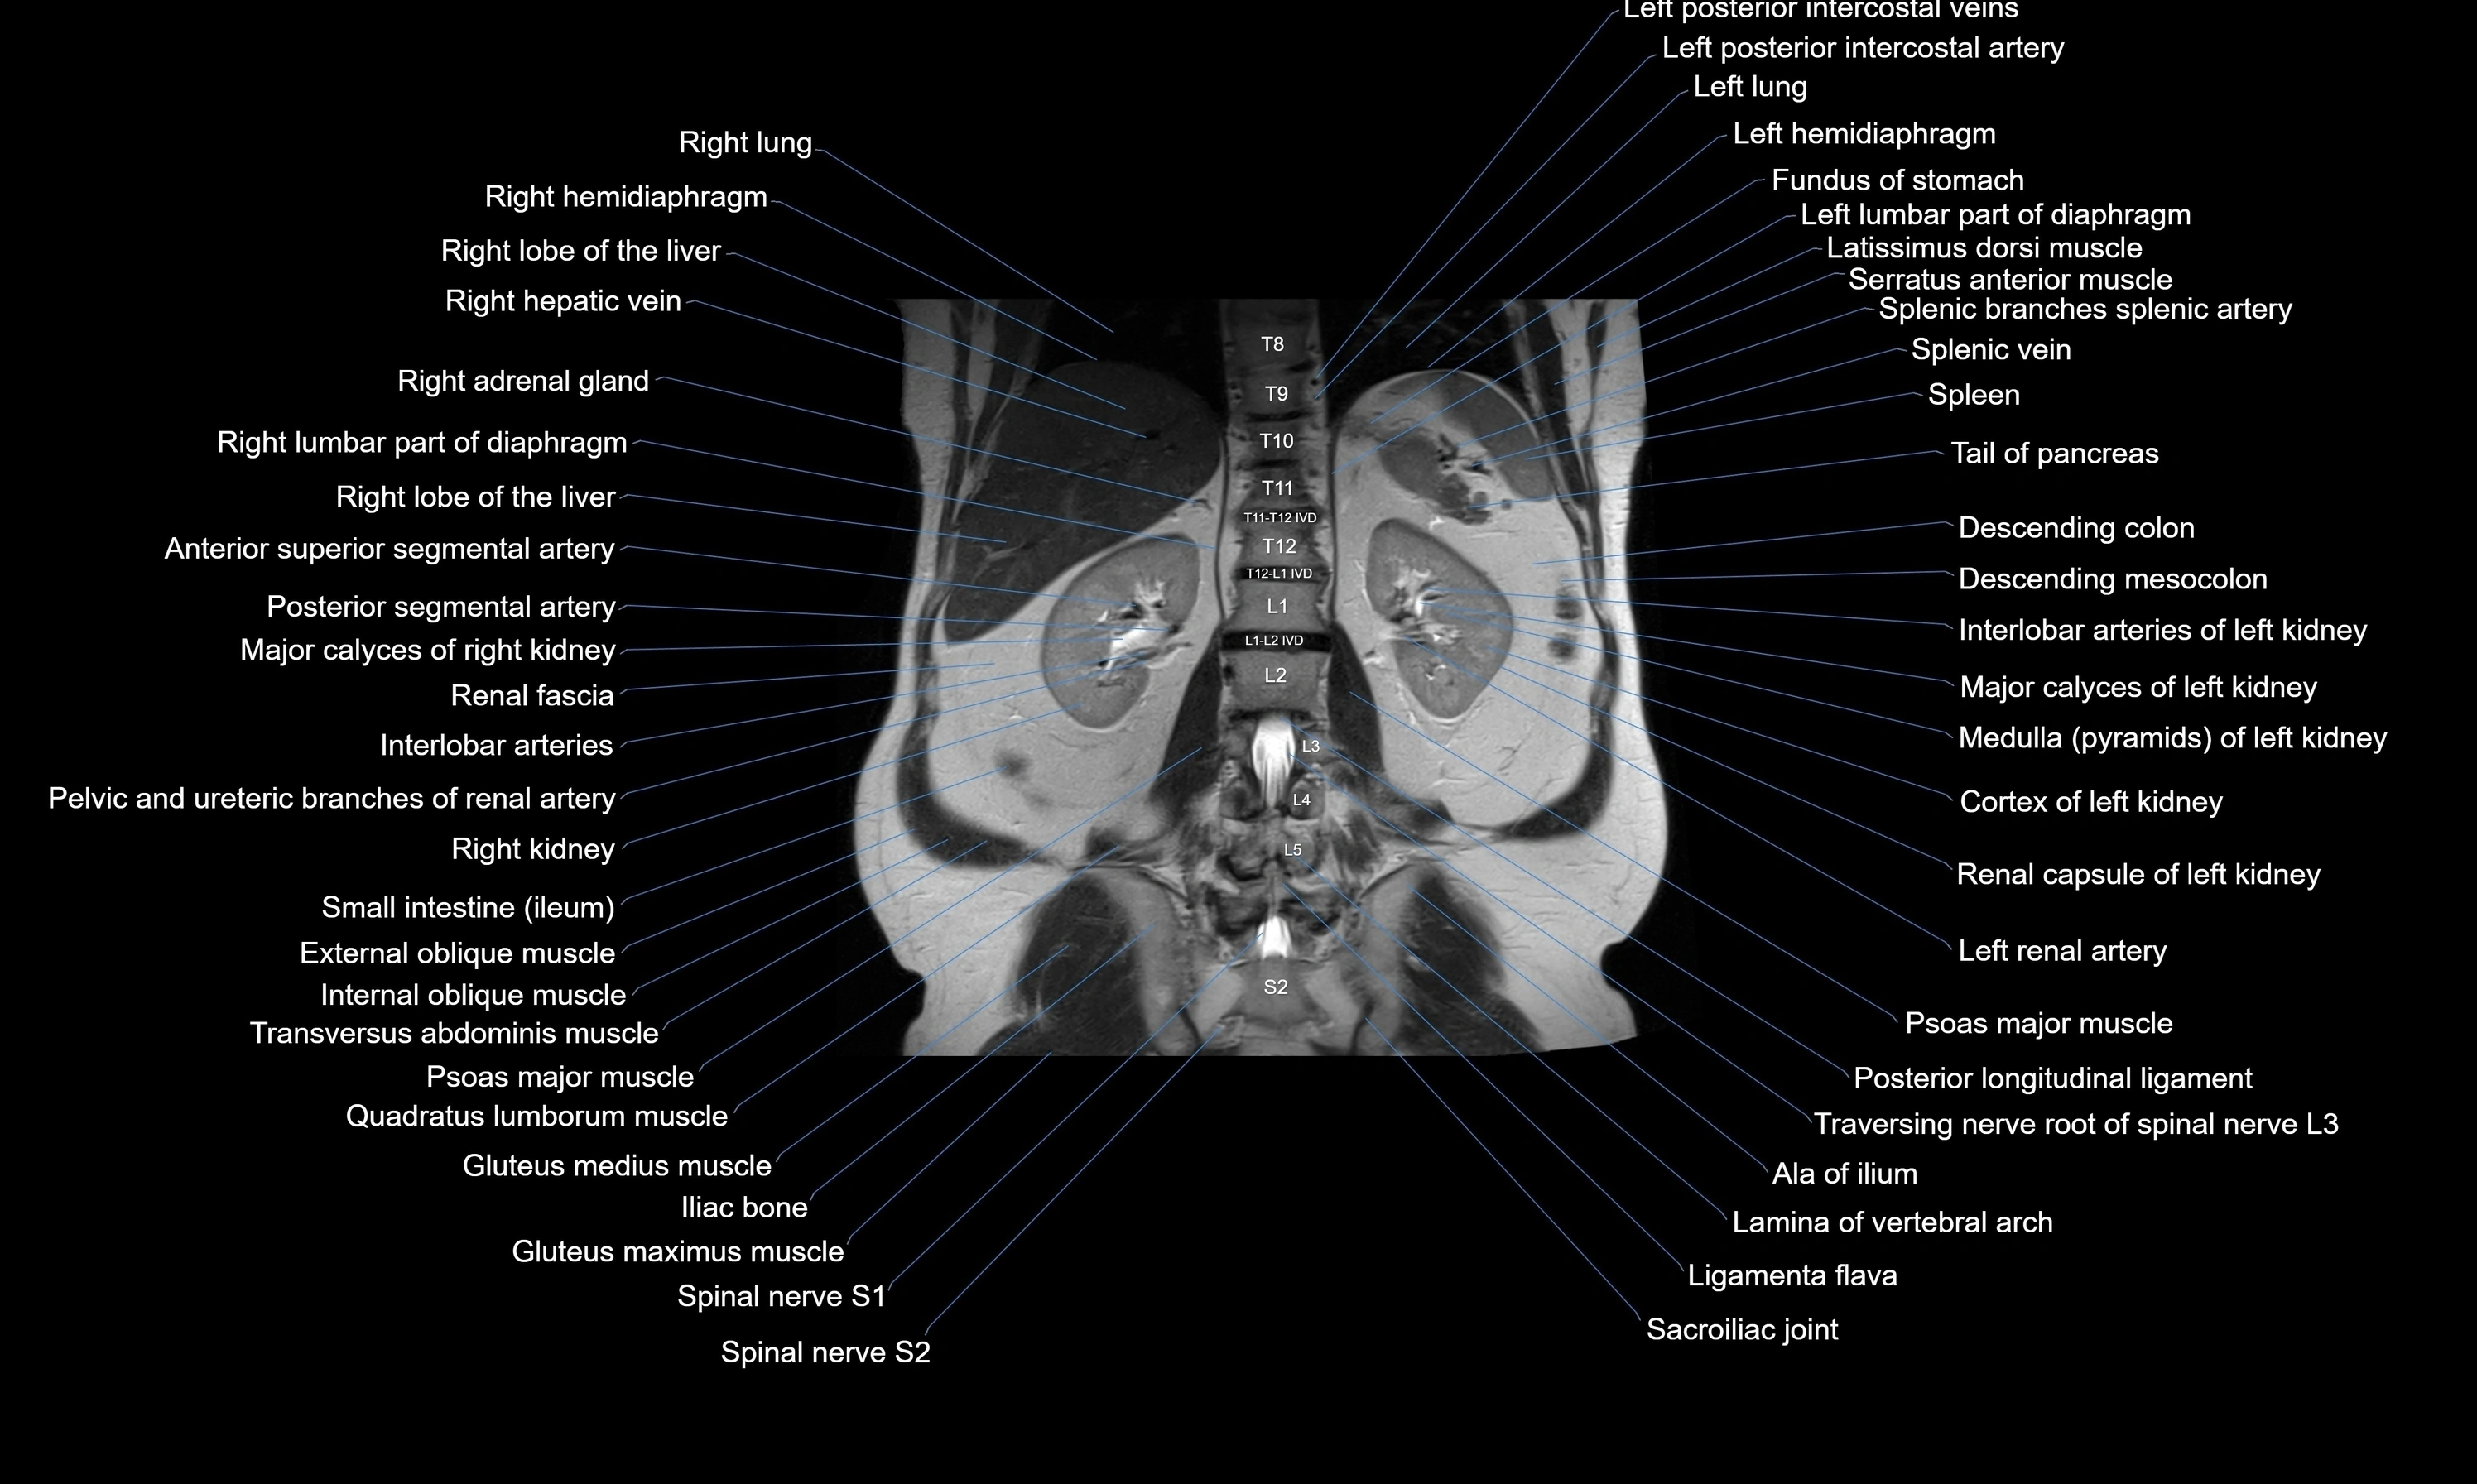

- kidneys

- Right kidney

- Left renal artery

- Psoas major muscle

- Quadratus lumborum muscle